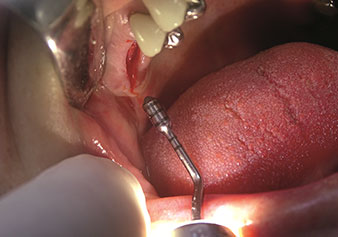

Indikation Interner Sinuslift

W&H bietet auch die perfekte Lösung für den internen Sinuslift an Nach der Kieferhöhlenpräparation mit dem

entsprechenden Instrumentarium (Abb. 3) erfolgt mit dem neuen Instrument Z35P (Abb. 4) die hydrodynamische Abhebung der Membran. Mit dem gleichen Instrumentenset kann auch die Implantatbett-Aufbereitung piezochirurgisch in aufsteigenden Durchmessern erfolgen (Abbildung drei und vier mit freundlicher Genehmigung von Dr. Mario Kirste, Frankfurt/Oder).